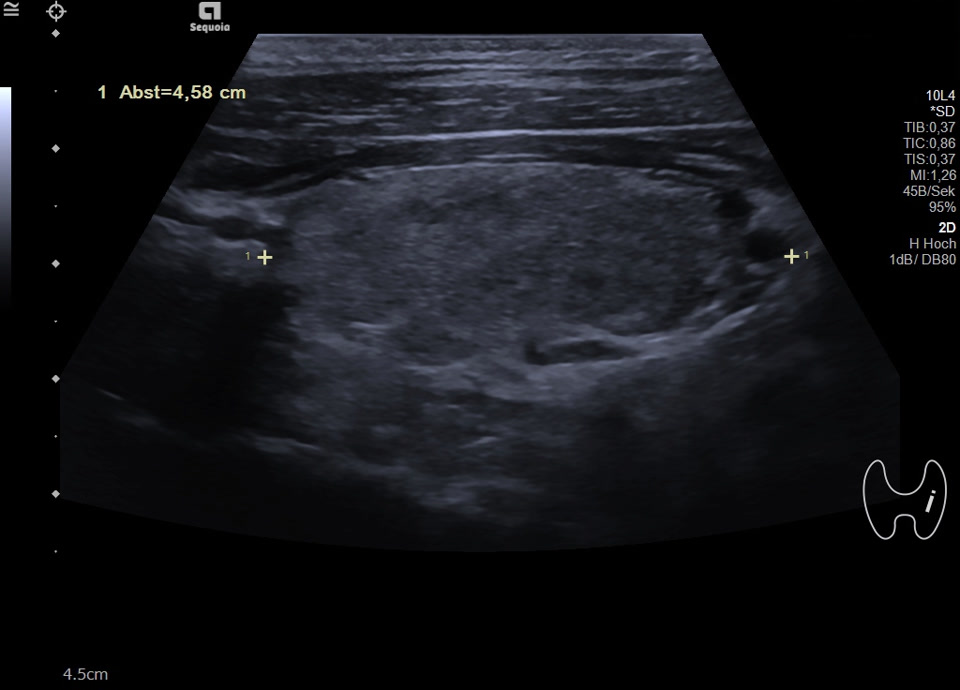

36-jähriger Patient mit Tremor, Tachykardie, Exophthalmus und Gewichtsverlust. Sonographisch stellt sich die Schilddrüse beidseits mit echoarmer inhomogener Parenchymstruktur dar. Gesamtvolumen 20,5 ml. Farbdopplersonographisch hypervaskularisiert. Laborbefunde: basales TSH erniedrigt, T3/fT4 erhöht, TRAK positiv. Befundkonstellation vereinbar mit M. Basedow. Unter Therapie mit Thiamazol und Propranolol beschwerdefrei. Bei Verlaufskontrolle zwei Jahre später sonographisch echoreiches minimal inhomogenes Parenchym bei normalem Volumen (15 ml).